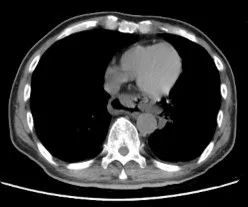

63歲男CT顯示遠端食道裂傷。阮綜合提供

阮綜合胸腔外科醫師林鴻生過年期間也曾支援急診,一位有中度三高狀況的63歲男性,與友人聚餐後接著續攤喝咖啡醒酒,回家後因嘔吐、腹痛腹脹、喉嚨和胸口疼痛送急診,診斷是自發性食道破裂,經手術與抗生素治療一個月才康復出院。

林鴻生醫師說,暴食飲酒後喝咖啡,容易在腹脹、嘔吐的瞬間造成食道損傷出血,此時仍積聚胸腔內的食物、胃液可能引起發炎造成敗血症。民眾歡慶年節的同時,宜節制飲食及酒量,想藉咖啡醒酒只會更刺激、增加心血管負擔,傷害更大。